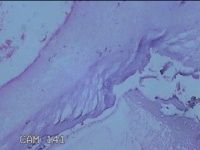

宫颈管内容物

性别

女

年龄

47岁

临床诊断

1.异常子宫出血 2.慢性宫颈炎

一般病史

不规则阴道流血21天。

标本名称

大体所见

灰白暗红色不规则碎组织1x0.5x0.3cm一堆。